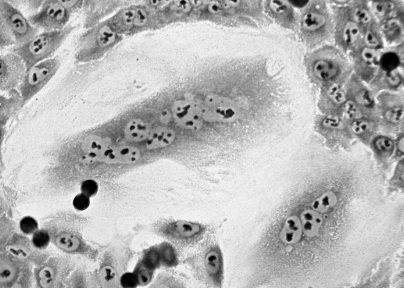

При наступлении благоприятных условий гигантская многоядерная клетка делится и дает начало потомству одноядерных клеток. Источник: Маргарита Пустовалова

Ученые исследовали опухолевые стволовые клетки. Ранее было известно, что они обладают высокой способностью восстанавливать повреждения ДНК и избегать клеточной гибели. Оказалось, что эти клетки также обладают способностью в стрессовой для себя ситуации уходить в особое спящее состояние - либо покоя, либо состояние называемое “преждевременным старением”. В этом  состоянии они переживают те дозы радиации, которые убивают обычные раковые клетки. А при наступлении благоприятного периода “просыпаются” и  дают популяцию многоядерных клеток, которые затем делятся, давая новые дочерние раковые  (в том числе стволовые) клетки и провоцируя таким образом рецидив болезни. Подобные популяции гигантских многоядерных опухолевых клеток обнаруживаются практически во всех опухолях.